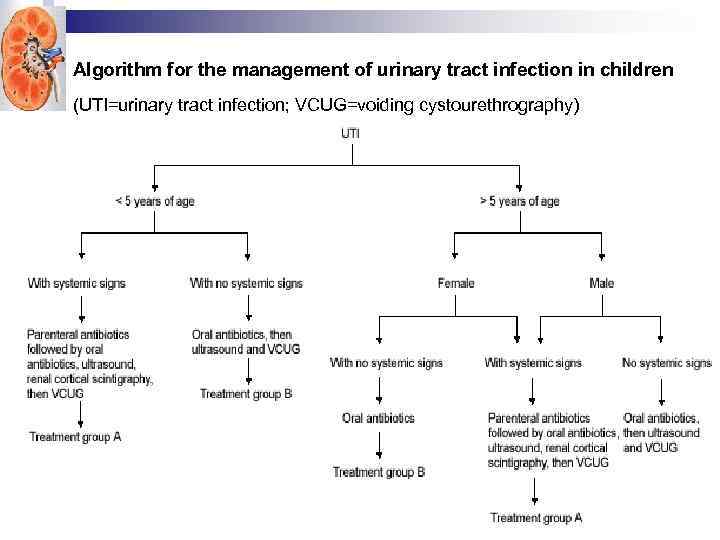

Algorithm for the management of urinary tract infection in children (UTI=urinary tract infection; VCUG=voiding cystourethrography)

Algorithm for the management of urinary tract infection in children (UTI=urinary tract infection; VCUG=voiding cystourethrography)